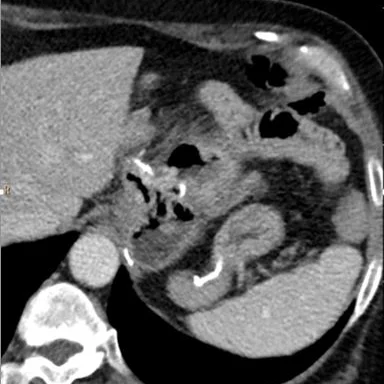

53 year old female with prior Roux-en-Y gastric bypass (6 years ago) and ongoing tobacco use presents with abdominal pain and melena. Hemoglobin  came back at 9.5 mg/dL. A CT scan was obtained. Conventional images show subtle abnormality at the gastrojejunostomy site. Iodine map shows clear large defect in wall enhancement adjacent to the GJ anastomosis, consistent with an ulcer.

Conventional CT. Staple line indicates the gastric bypass.